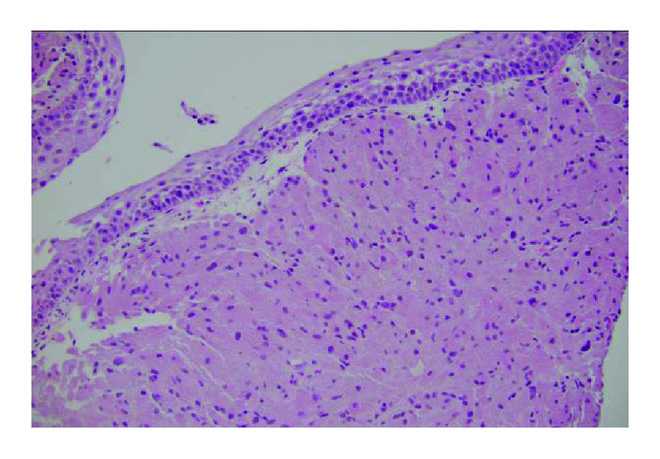

The infiltrative nature of pulmonary GCTs is a well-established feature for this benign tumor [2]. Peribronchial tissue extension has been reported in up to 40% of tumors as these tumors like to grow along muscle fibers, fibrous septa, and nerve sheath bundles [2]. Pseudoepitheliomatous hyperplasia, an overgrowth or thickening of the overlying squamous epithelium (Figure 8), is a diagnostic feature seen for these tumors. Microscopically, the tumor is composed of abundant eosinophilic granular cytoplasm, with fairly uniform arrangement of small nuclei. GCT is mostly benign, with malignant course occurring in 2% of cases [10]. Differentiation between benign and malignant GCTs is often difficult. Six histologic features have been described which can predict malignant potential of GCTs. These features include spindling of the tumor cells, the presence of vesicular nuclei with large nucleoli, increased mitotic rate (>2 mitoses/10 high-power fields at 200x magnification), a high nuclear-to-cytoplasm (N : C) ratio, pleomorphism, and necrosis. Histologically, malignant GCT is diagnosed when three or more of the six criteria are fulfilled [11]. Our case did not fulfill the criteria for malignant GCT.